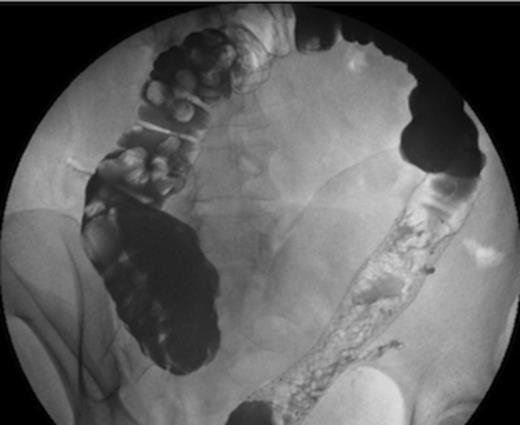

A month later, contrast studies showed complete resolution of the anastomotic stricture and no evidence of colo-cutaneous fistula (Figure 2). The SEMS was hence removed. At a clinic review one year post Hartmann’s reversal, the patient remained asymptomatic and the fistula had resolved both clinically and radiologically.